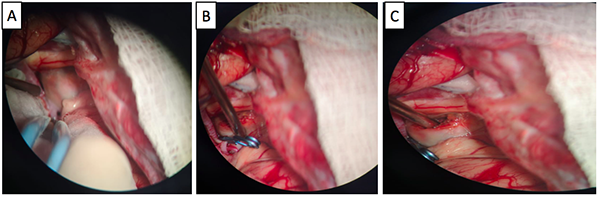

Paciente de género femenino, de 51 años de edad, que consultó a oftalmología por un cuadro clínico de 20 días de evolución consistente en disminución súbita de la agudeza visual del ojo derecho, no asociado a dolor, síntomas sistémicos, ni compromiso de los movimientos oculares. En la evaluación  inicial se encontró en el ojo derecho un defecto pupilar aferente, agudeza visual mejor corregida de 20/400, discromatopsia con test de Ishihara 0/14,  y excavación del 20% en el borde del disco óptico, compatibles con neuritis óptica retrobulbar. En la campimetría por confrontación, se encontró una hemianopsia temporal derecha. A su ingreso a urgencias se le realizó tomografía de cráneo en la que se encontró lesión selar y supraselar, por lo cual se solicitó RMN cerebral contrastada bajo la sospecha de un macroadenoma hipofisiario. En la RMN (Ver Imagen 1) se identificó lesión ovalada, de localización supraselar, con efecto de masa sobre el quiasma óptico y la porción cisternal de ambos nervios ópticos, principalmente del lado derecho, con cambios en secuencias de susceptibilidad, compatible con aneurisma de la AComA parcialmente trombosado.

Figura 1

. RMN de cráneo en la que se identifica lesión sacular de localización supraselar con efecto de masa, mide 22 mm x 19 mm x 17 mm (A), desplaza y comprime el quiasma óptico y la porción cisternal de ambos nervios ópticos, especialmente el del lado derecho (B), tiene un área en forma de media luna que realza tras la administración del medio de contraste (B y C). En la parte inferior se observa la Arteriografía cerebral con un aneurisma sacular de contornos irregulares, localizado en el segmento comunicante anterior de 8mm x 6mm x 5 mm (D, E y F).

Para definir con mayor detalle la anatomía vascular, se realizó una arteriografía (Ver Imagen 1), con la que se confirmó la presencia de un aneurisma sacular de la arteria comunicante anterior, de contornos irregulares, de 8x6x5 mm, sin signos de ruptura con una orientación antero-inferior. Esta clara diferencia entre el tamaño de la lesión en la RNM y la arteriografía confirma la presencia de un trombo intra-aneurismal.